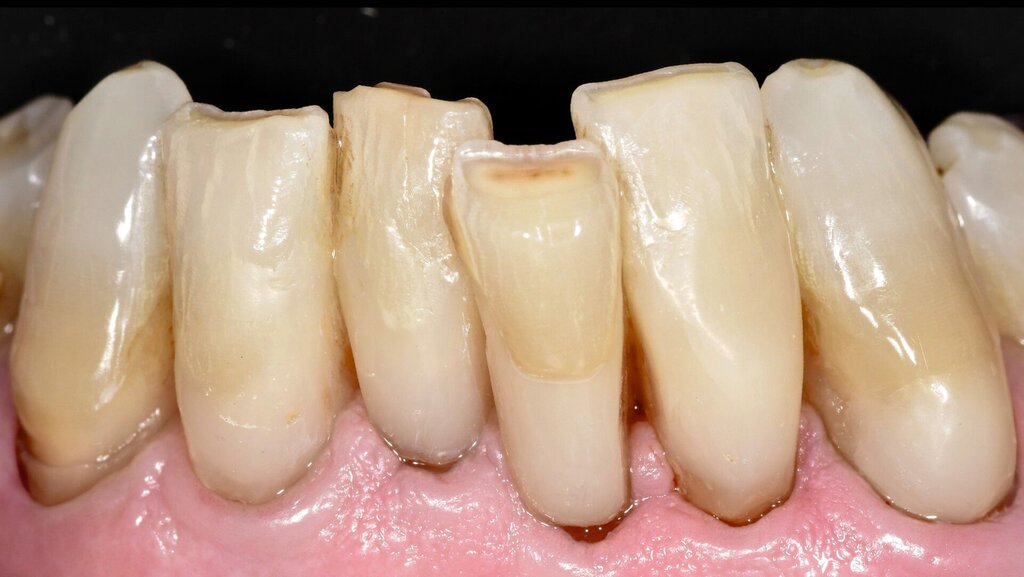

Die Zähne reagierten positiv auf einen Sensibilitätstest mit Kältespray und wiesen Sondierungstiefen von 2-3 mm Tiefe auf. Die Zähne wurden wie nachfolgend beschrieben versorgt. Nach fünf Jahren Beobachtungszeit sind die Restaurationen des nun 80-jährigen Patienten bis auf kleine Defekte im zervikalen Anteil als akzeptabel einzustufen. Die Gingiva weist eine über die Beobachtungszeit leicht progrediente Rezession auf.

Abbildung 3 zeigt einen weiteren Fall nach sieben Jahren Tragedauer, bei dem die beschriebene Technik bei der Füllungslegung zur Anwendung kam.